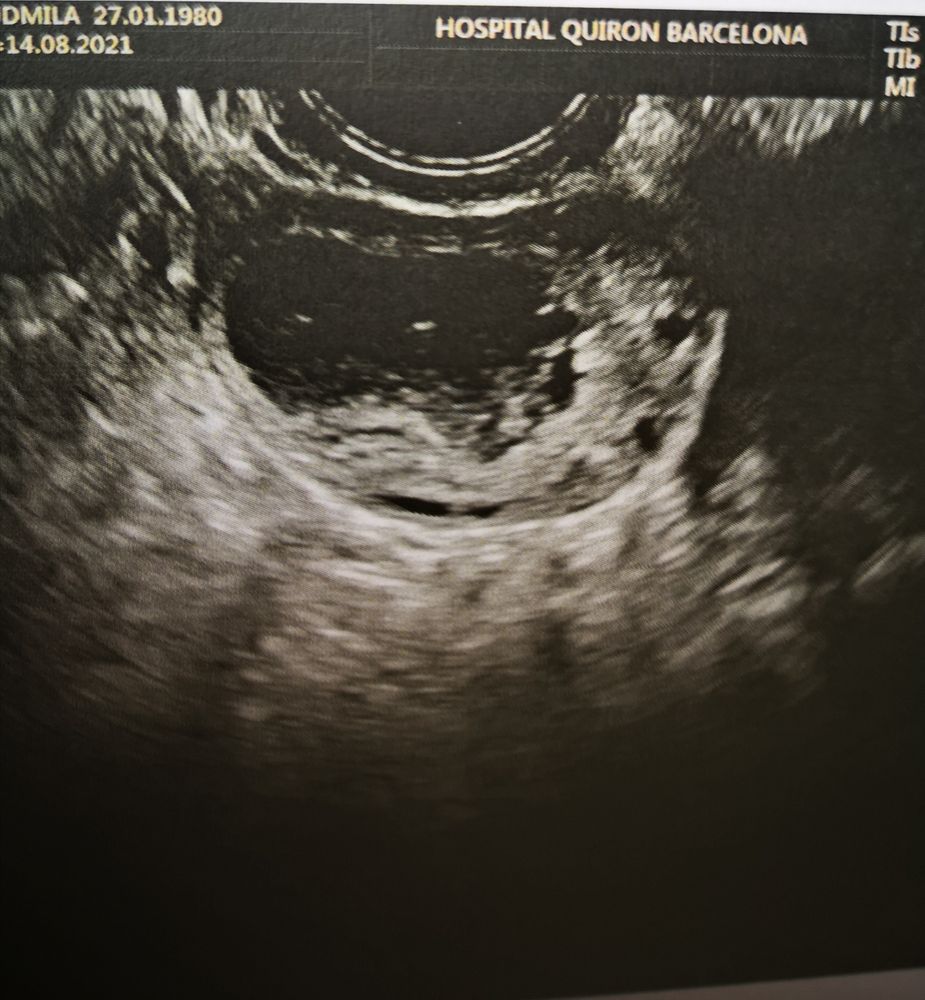

Жт или лютинизация фоликула?

Скоро два раза мама!!!))), ну у меня 1 дпо получается 20 мм. У меня лопаются 22-24 мм, на 4 дпо уже 26. Ну я так понимаю жт и лютинизированый фоликул трудно отличить. Надо сразу в день О смотреть. Просто на 1 дпо мне вообще левый врач смотрел.

Мила, у меня как-то в цикле стимуляции непонятки тоже были с УЗИ. В итоге пошла на экспертное УЗИ, дороговато конечно чем обычно, но хоть все по полочкам разложили. В итоге было 1 ЖТ, 1 лютеинизировавшийся фолликул и 1 в регресс ушел. По изображению лютеинизировавшийся фолликул и ЖТ очень похожи по мне, но врачи их как-то различают по кровотоку, содержимому и т.д.